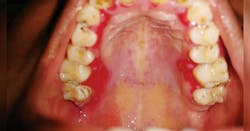

Figure 2: Gingival MMP. Courtesy Of Nancy W. Burkhart, RDH, EdD.

Figure 1 depicts the palatal lingual gingiva with extreme redness. Figure 2 depicts the gingival areas in a patient with MMP with epithelial stripping around the margin of #7. Figure 3 depicts the scarring of the eye and symblepharon/entropion and adhesion of the eye.